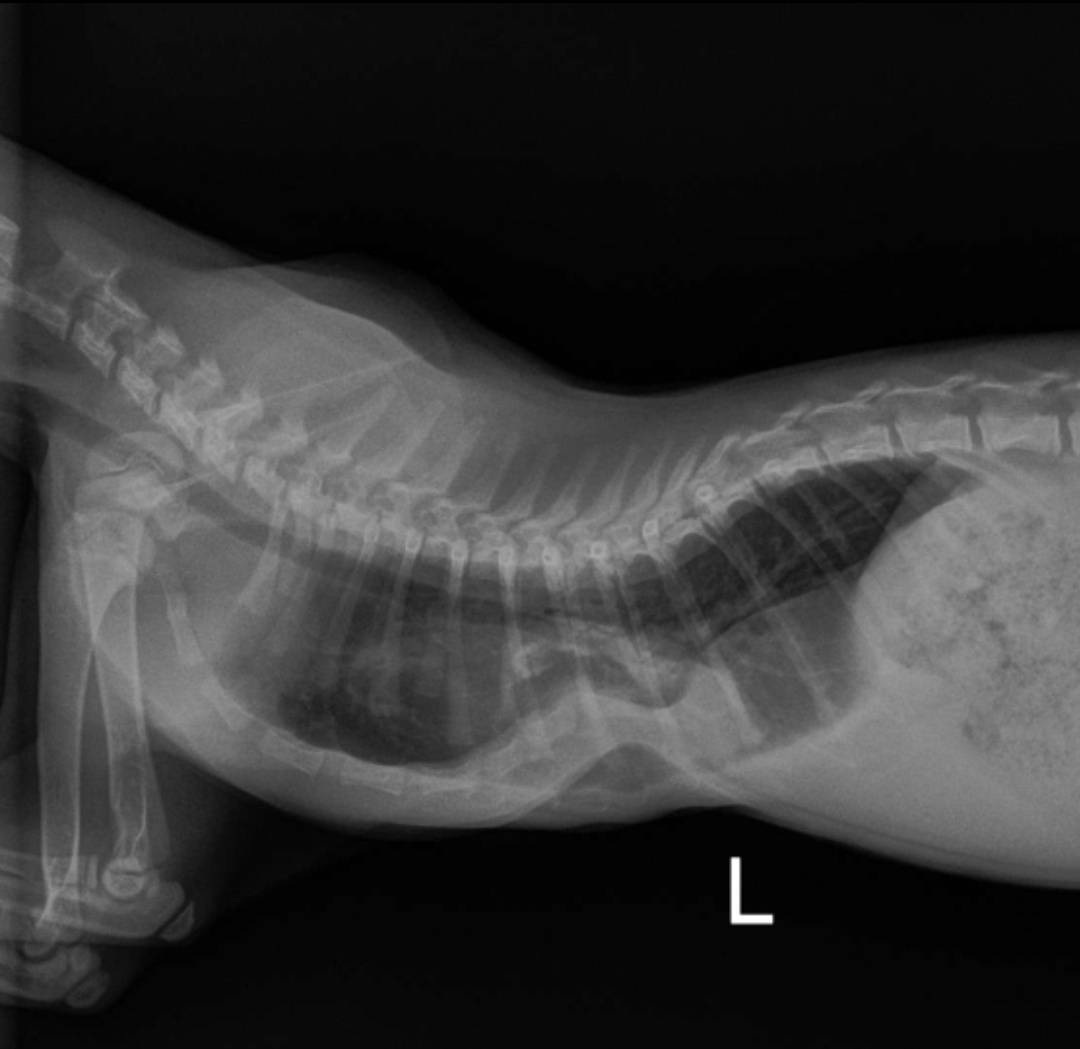

Mavis has a condition called pectus excavatum—a congenital deformity that causes her breastbone to grow inward. In her case, her chest was pressing on her lungs, heart, and esophagus, making it hard for her to breathe, eat, and grow like a normal kitten.

Second appointment, x-ray with contrast: 197.03